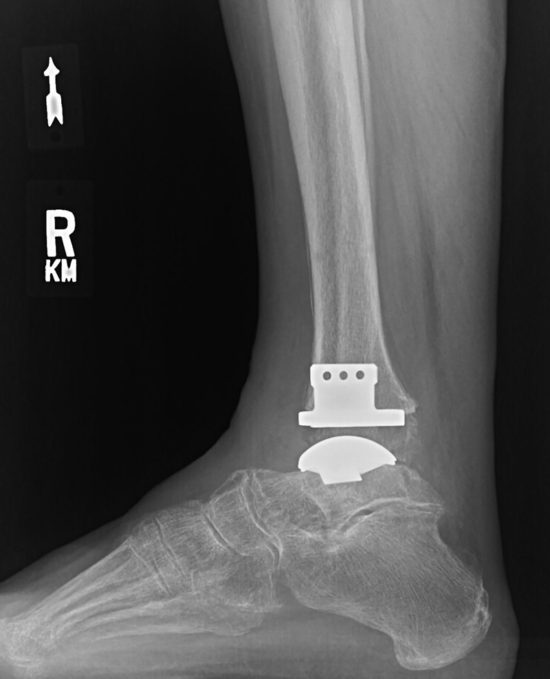

TAA uses a 2-part or 3-part implant to resurface the ends of the tibia and the talus with metal components and a synthetic piece positioned between them, allowing joint movement. TAA offers greater ankle range of movement than AA and can therefore improve gait, decrease stress on other joints, and potentially lead to less arthritis in surrounding joints; however, complications include implant loosening, ankle instability, osteolysis, infection, and a need for reoperation.3,8,12